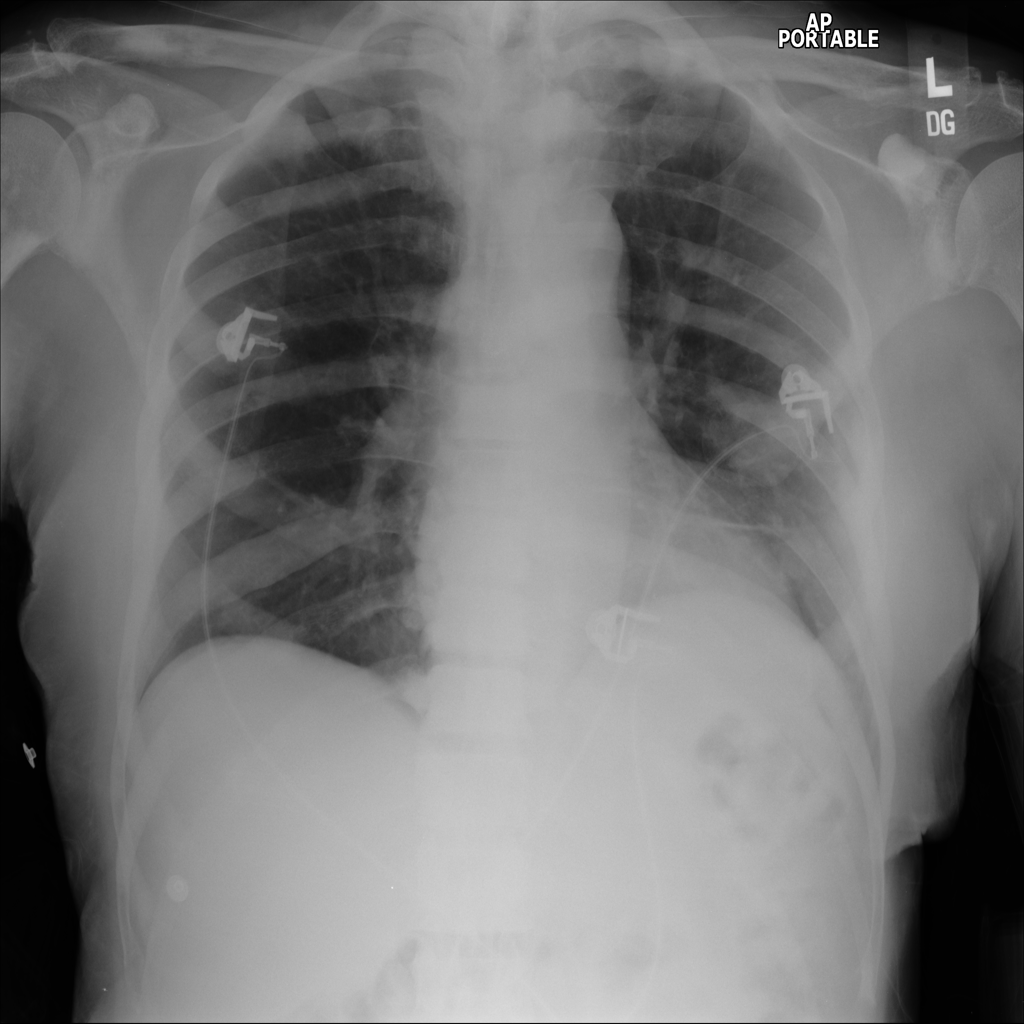

PAT-DB80 · IMG-000Atelectasis

PAT-DB80 · IMG-000

PA